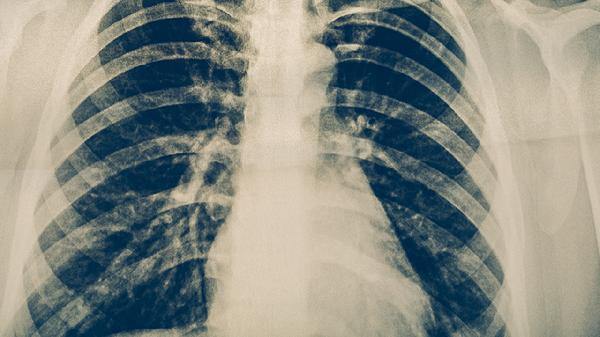

1、呼吸衰竭

多器官功能障碍综合症患者早期可能出现呼吸急促、血氧饱和度下降等表现,随着病情进展可发展为急性呼吸窘迫综合征。肺部听诊可闻及湿啰音,动脉血气分析显示低氧血症。临床常用无创呼吸机辅助通气,严重者需气管插管连接有创呼吸机治疗。药物方面可遵医嘱使用注射用甲泼尼龙琥珀酸钠、盐酸氨溴索注射液、注射用头孢哌酮钠舒巴坦钠等。